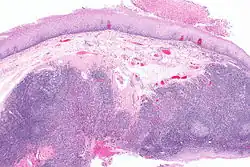

Diagnosis of oral cancer is completed for (1) initial diagnosis, (2) staging, and (3) treatment planning. A complete history, and clinical examination is first completed, then a wedge of tissue is cut from the suspicious lesion for tissue diagnosis. This might be done with scalpel biopsy, punch biopsy, fine or core needle biopsy. In this procedure, the surgeon cuts all, or a piece of the tissue, to have it examined under a microscope by a pathologist.[45] Brush biopsies are not considered accurate for the diagnosis of oral cancer.[46] Salivary biomarkers are also being under investigation with emerging outcomes and could potentially be used as a non-invasive diagnostic tool in the future.[47]

With the first biopsy, the pathologist will provide a tissue diagnosis (e.g. squamous cell carcinoma), and classify the cell structure. They may add additional information that can be used in staging, and treatment planning, such as the mitotic rate, the depth of invasion, and the HPV status of the tissue.

From these collective findings, taken in consideration with the health and desires of the person, the cancer team develops a plan for treatment. Since most oral cancers require surgical removal, a second set of histopathologic tests will be completed on any tumor removed to determine the prognosis, need for additional surgery, chemotherapy, radiation, immunotherapy, or other interventions.